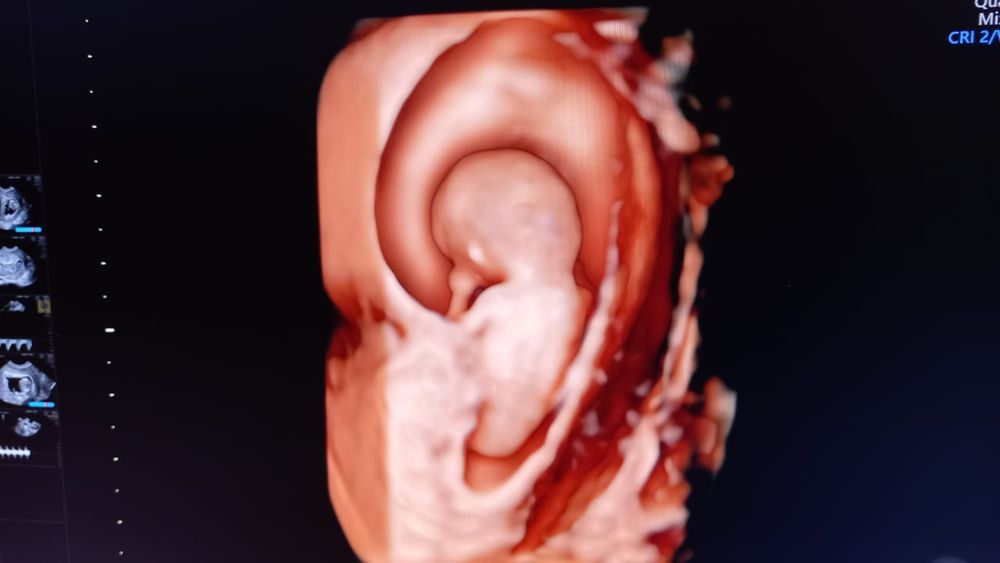

Наш мыслитель уже о чем то там думает:

Ни в какую не хотел разворачиваться. Меня даже гулять отправляли,водички попить, по лестнице погулять.